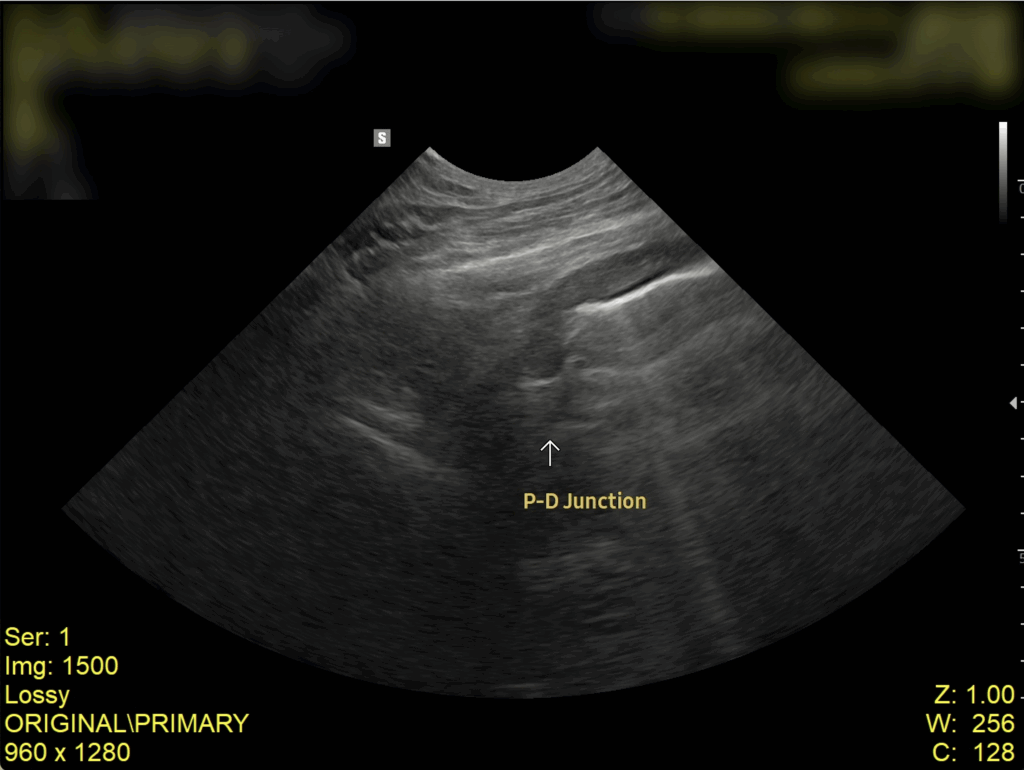

복부 초음파 검사 결과

초음파 검사 결과, 복강 내 림프절이 비대된 모습이 확인되었고, 장벽 두께가 정상보다 두꺼워진 것을 확인되었습니다. 이는 장 내 염증 반응이나 감염성 원인에 의해 장벽이 자극을 받고 있음을 의미합니다.